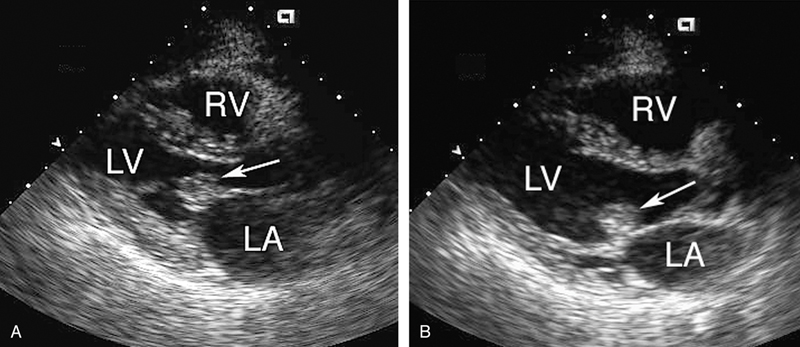

فحوصات تشخيصية لبعض امراض القلب والشرايين التاجية